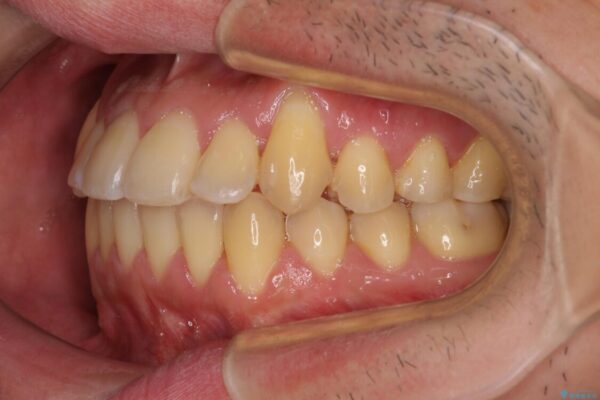

八重歯と前歯のクロスバイトを改善したいとのことで来院された患者様です。

デコボコの程度は強かったのですが、口元の突出感はなかったため、非抜歯矯正としました。

治療前

• 八重歯とクロスバイト 目立たないワイヤー装置で矯正治療 治療前画像